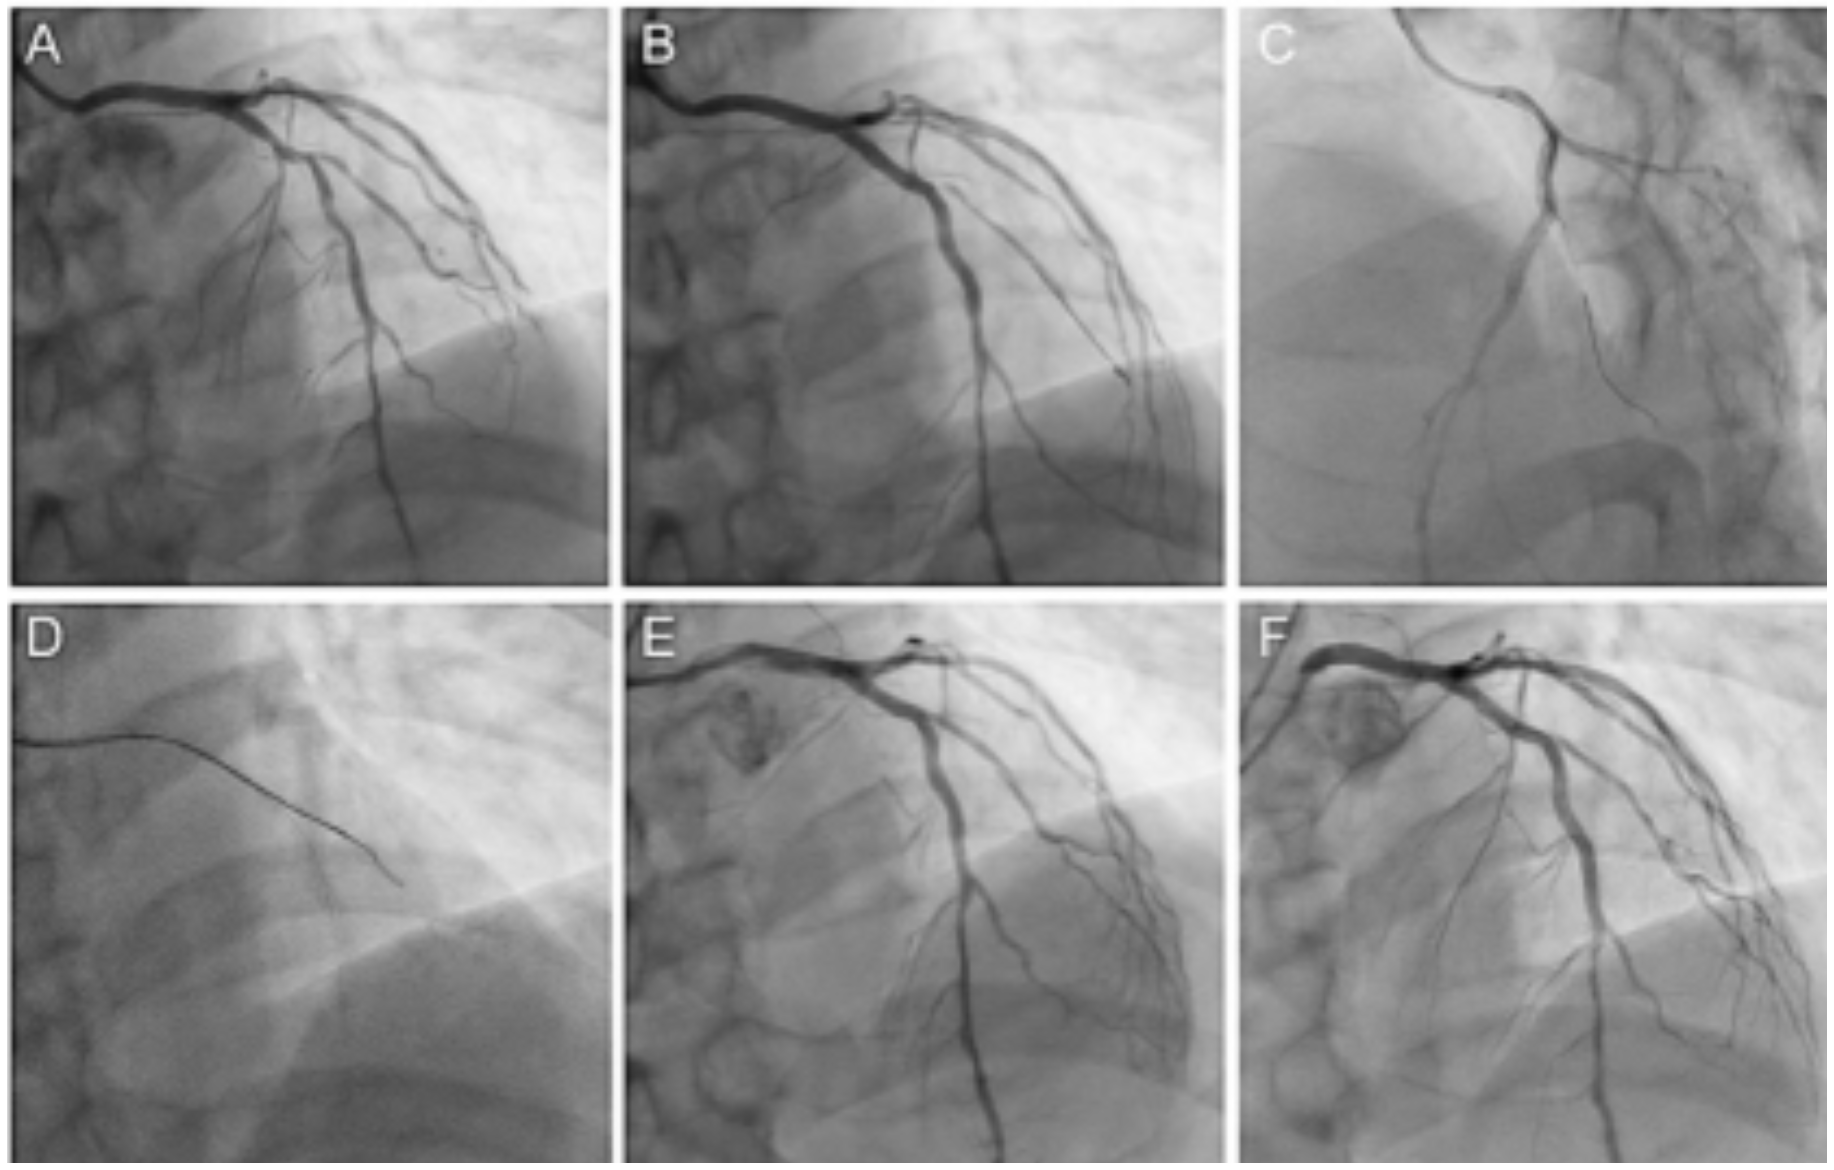

When the SB was impaired, we first attempted to recross the SB with conventional strategies, such as using a floppy guidewire with a dual-lumen catheter (Figures 1A, 1B). If failure occurred, we used a polymer-jacketed guidewire, such as the Sion Black (Asahi Intecc) or XT-R (Asahi Intecc) with a dual-lumen catheter. If that did not work either, and if the guidewire advanced into the subintimal space, SB-STAR was performed as a bailout strategy (Figure 1C). SB-STAR was performed using a floppy or polymer-jacketed guidewire with a microcatheter (Figure 1D). The type of guidewire used was at the discretion of the operator. A typical case using the SB-STAR is shown in Figure 2.